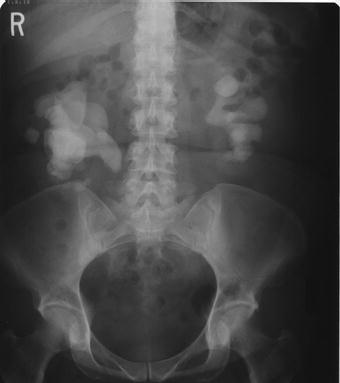

Figure 2.1 Plain abdominal x-ray demonstrating full bilateral staghorn calculi.

Although magnetic resonance imaging (MRI) provides excellent soft tissue imaging, its use in the evaluation of staghorn calculi has been limited due to poor visualization of stones, high cost, long acquisition time, and degradation with motion artifact [15,16]. Ultrasound is able to accurately detect renal calculi, determine parenchymal thickness and access for hydronephrosis without ionizing radiation. A KUB is also routinely performed to give an overview of the stone size and location, and to determine whether the stone is radiopaque (Figure 2.1). A nuclear renogram may be helpful to access renal function in staghorn patients, particularly in those with long-standing hydronephrosis, parenchymal thinning or prior interventions [17].